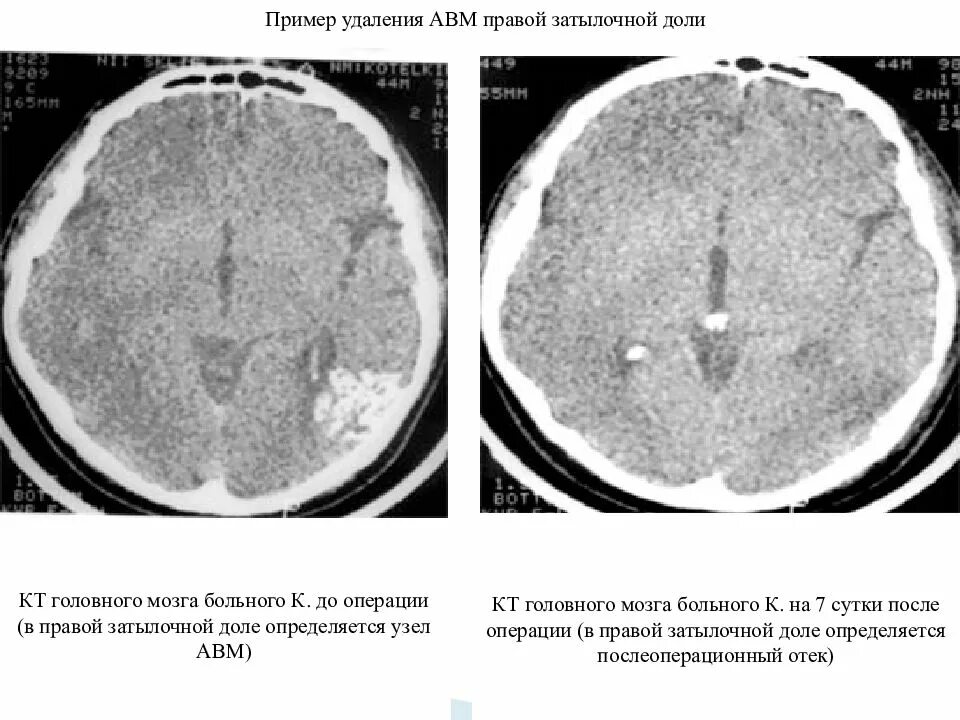

Мальформация сосудов